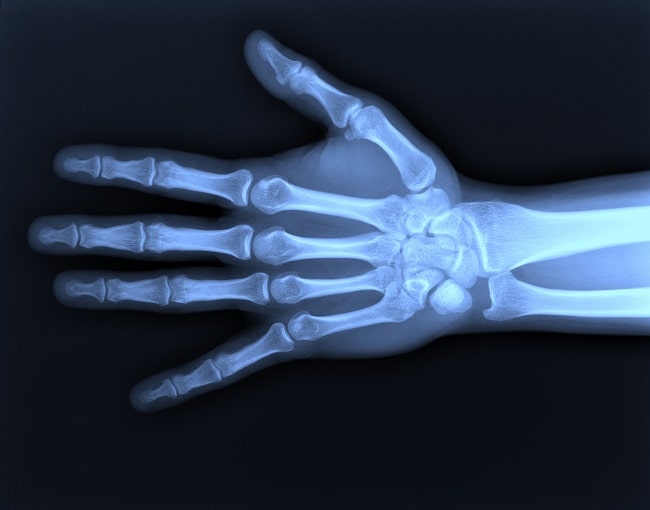

Rontgen tangan adalah suatu prosedur radiologi diagnostik untuk penilaian fraktur, dislokasi, dan trauma akut pada jari, tangan, pergelangan tangan, serta sebagian lengan bawah. Selain itu, rontgen tangan juga digunakan untuk mendeteksi kelainan degeneratif seperti osteoarthritis, gangguan metabolik seperti hiperparatiroidisme, serta infeksi dan tumor pada area tersebut.[1]

Rontgen tangan merupakan suatu modalitas pemeriksaan penunjang radiologis berbasis sinar-X yang berperan dalam evaluasi kelainan dan patologi pada struktur tulang dan jaringan lunak di tangan. Pemeriksaan rontgen tangan sering menjadi pemeriksaan inisial yang dipilih untuk menilai kelainan pada tangan. misalnya pada pasien yang mengalami nyeri setelah trauma untuk mengevaluasi fraktur, pada pasien dengan kecurigaan rheumatoid arthritis atau osteoarthritis, ataupun pada kasus kecurigaan massa.

Meskipun demikian, rontgen tangan memiliki beberapa keterbatasan. Oleh karena pada tangan terdapat berbagai struktur yang bertumpang tindih, beberapa jenis fraktur tidak dapat terlihat secara jelas melalui rontgen tangan. Fraktur tulang lunatum, triquetrum, kapitatum, skafoid, dan hamatum sangat sulit didiagnosis melalui radiografi.

Radiografi konvensional juga memiliki sensitivitas yang rendah dalam mendeteksi fraktur stres dini (early stress fracture). Selain itu apabila pada rontgen tangan tampak area pembengkakan atau kelainan jaringan lunak (soft tissue swelling or abnormalities) yang mungkin menandakan adanya cedera jaringan lunak (soft tissue injury), sebaiknya dievaluasi dengan modalitas pencitraan yang lebih mutakhir, seperti MRI.[2]